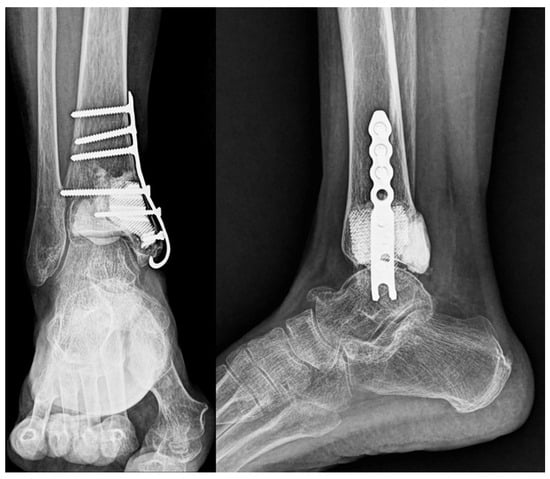

Postoperative radiographs confirmed stable prosthesis placement and proper alignment (Figure 8). The pathological findings were consistent with low-grade chondrosarcoma (Grade I).

Figure 8. Postoperative imaging. Postoperative radiographs of the ankle in anteroposterior and lateral views showing stable fixation with a locking plate with proper prosthesis placement.